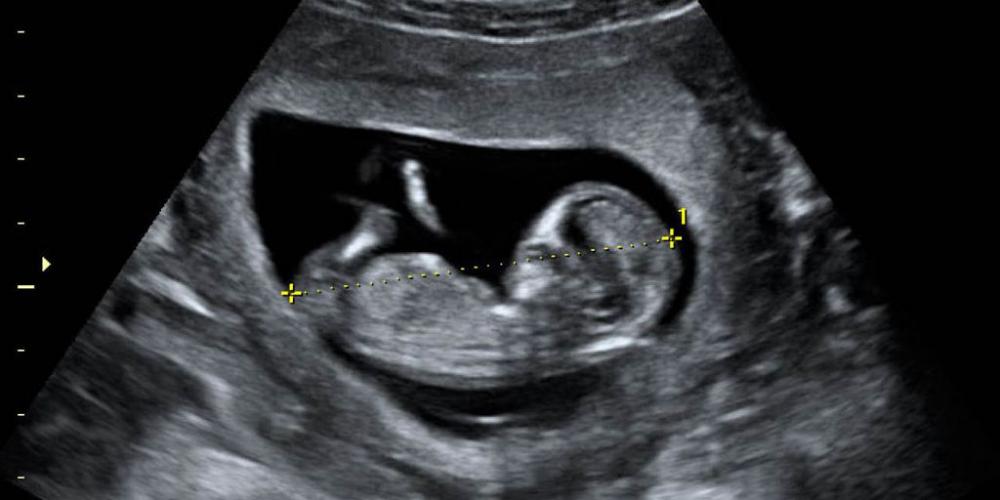

1.000 NIÑOS NACIDOS GRACIAS A LA AYUDA A SUS MADRES

La Red Nacional de Acompañamiento a la Mujer con embarazo vulnerable, que reune a 472 instituciones del país, está cumpliendo 42 meses de un trabajo que ha permitido el nacimiento de 1.000 argentinos. ¨¡Seguimos...

EN BUENOS AIRES MUEREN MÁS DE 90 NIÑOS ANTES DE NACER POR DÍA

En 2021 el 92% de los abortos en la provincia de Buenos Aires se hicieron con la droga Misoprostol. Desde que Axel Kicillof (50) gobierna la provincia de Buenos Aires fueron incorporados 298 nuevos sitios (hospitales...